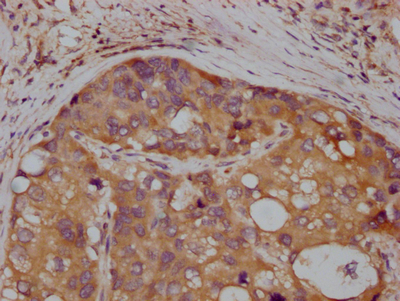

IHC (Immunohistochemisry)

(IHC image diluted at 1:100 and staining in paraffin-embedded human liver cancer performed on a Leica BondTM system. After dewaxing and hydration, antigen retrieval was mediated by high pressure in a citrate buffer (pH 6.0). Section was blocked with 10% normal goat serum 30min at RT. Then primary antibody (1% BSA) was incubated at 4 degree C overnight. The primary is detected by a Goat anti-rabbit IgG polymer labeled by HRP and visualized using 0.05% DAB.)